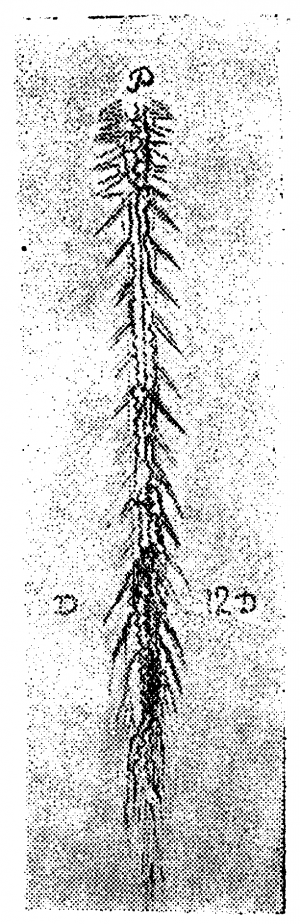

Вены поверхности спинного мозга (рис. 2). Вены мягкой мозговой оболочки, как и артерии, расположены преимущественно продольно, но число венозных стволов гораздо менее постоянно, чем артериальных. Даже на одном препарате на разных уровнях оно различно. Вены змеятся вдоль спинного мозга, иногда сплетаясь в «нераспутываемый клубок», как выражается Адамкевич. Строго говоря, на поверхности спинного мозга существует настоящее венозное сплетение, аналогичное сплетениям позвоночного канала. Число, калибр и расположение отдельных стволов венозного сплетения спинного мозга подлежат очень большим колебаниям.

Мы уже неоднократно упоминали о работе Словохотова, исследовавшего развитие сосудов спинного мозга в эмбриональный период и показавшего, что закладка сосудов в эмбрионах проходит по эмбриональному типу, который ещё ясно выражен до 6-го лунного месяца. Во вторую половину утробной жизни происходит перестройка метамерного типа на стволовой (рис. 3 и 17).

По нашим исследованиям, у новорожденных строение вен спинного мозга уже приобретает все основные характерные черты, свойственные взрослому; мы можем совершенно определённо констатировать наличие продольных стволов, вены корешков выражены ясно, неравномерны по калибру и неравномерно распределяются.

В возрасте 4—5 месяцев внеутробной жизни, мы видели уже богато развитую поверхностную венозную сеть, но она ещё очень тонка, почти капиллярна. Передний средний венозный тракт вполне сформирован; боковые тракты намечаются на нашем препарате спереди, в грудном отделе спинного мозга. Вены спинно-мозговых корешков выражены хорошо, но ещё сохраняют эмбриональный тип в том отношении, что вены главных оттоков (корешков шейного и поясничного утолщения) ещё не так резко преобладают над другими корешковыми венами, как это бывает у взрослых.

Большая вена Адамкевича типично отходит от среднего переднего венозного тракта, очень хорошо развитого.

Задняя поверхность мозга на том же препарате представляет более пёструю картину: шейная часть задней поверхности покрыта тончайшей сетью вен, но продольное расположение сосудов по корешкам и задней расщелине уже намечается. Грудная часть препарата особенно интересна: с 8-м шейным корешком отходит (типично) вена спинно-мозгового нерва; сверху она соединена с венозными стволиками шейной сети, а книзу проходит в виде крайне извитого, часто пересекающего медиальную линию сосуда. Вены некоторых корешков (например, 2, 4 грудного) начинаются двумя корнями — верхним и нижним, так что намечается боковой тракт. Средний венозный тракт выравнивается в грудной области и змеится вдоль средней линии, причём на протяжении 6—7 грудных сегментов его сопровождает параллельный, уже хорошо сформированный стволик, спускающийся вдоль входа в мозг задних корешков. Оттоки в поясничной области развиты хорошо на 12-м грудном справа и на 1—2-м поясничных корешках слева.